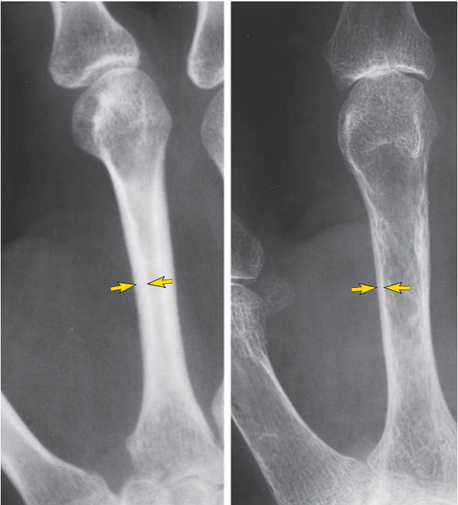

Рентгенограмма середины второго метакарпального фаланга лица с нормальной минерализацией (слева) и пациента с тяжелым остеопорозом (справа). При нормальном состоянии кортикальная толщина (стрелки) более, чем 1/3 общей толщины метакарпального фаланга, тогда, как при остеопорозе экстримально тонкая.